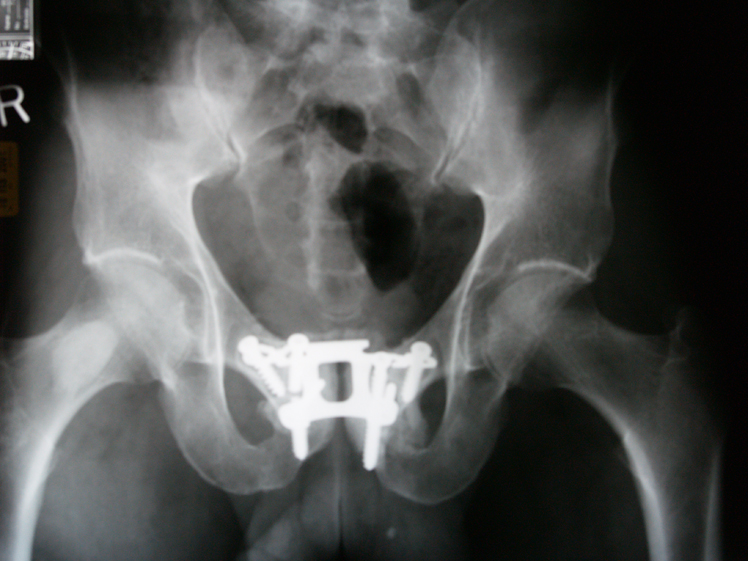

Now, here’s the rub. During the Stone Age, during 99.9 % of human existence on earth, when most of evolutionary development happened, people rarely lived past 40 years old. So….our knees, elbows, backs, hips, and ankles were designed to last that long. You get my drift. I’m 67 years old and I know a whole lot of geezers who still ski, climb, hike, ride mountain bikes, and so on. In fact, almost every geezer I know has worn out their bodies in some way — and been lucky enough to have had the original-issue, bone and cartilage, parts repaired or replaced with titanium and Teflon. It goes with the territory.

In a normal year, I’d still be skiing, but instead I am in Grand Junction, Colorado with my wife, Nina, being her buddy as she prepares for back surgery. As far as the doctors can surmise, she broke a bone in her lower back a long time ago, possibly when she fell off a horse when she was 15. Anyway, her back has been slowly slipping out of alignment for over 40 years until this winter, the vertebrae started pressing against nerves. Ouch.